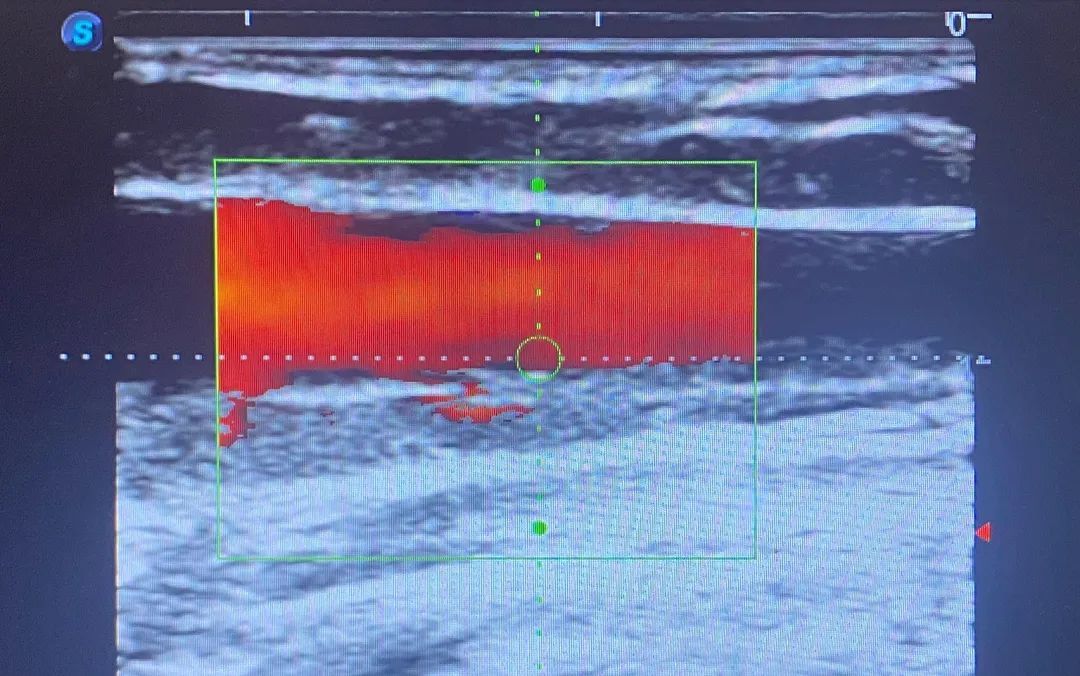

术前B超显示静脉血栓形成、狭窄闭塞

▲术后B超显示血流畅通